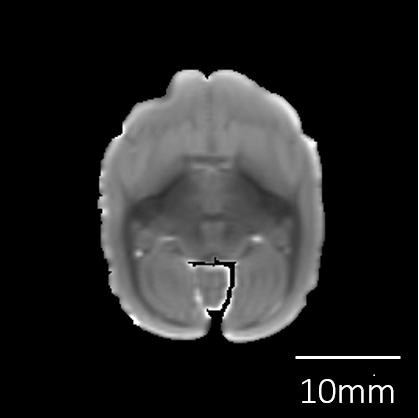

| 脳重量 | 4.1g | |

撮像情報

| T2強調画像 | 拡散テンソル画像 | |

| エコー時間 (TE) (秒) | 7 | 19.5 |

| 繰り返し時間 (RT) (秒) | 600 | 500 |

| 励起回数 (NEX) | 4 | 3 |

| 有効視野 (FOV) (mm) | 36, 32, 19.2 | 36, 32, 19.2 |

| マトリクスサイズ | 240, 214, 128 | 120, 106, 64 |

| 空間分解能 (µm) | 0.15, 0.15, 0.15 | 0.3, 0.3, 0.3 |

| b0 | - | 2 |

| 撮像時間 | 9時間 53分 | 68時間 16分 |

脳標本画像

| T2強調画像 |